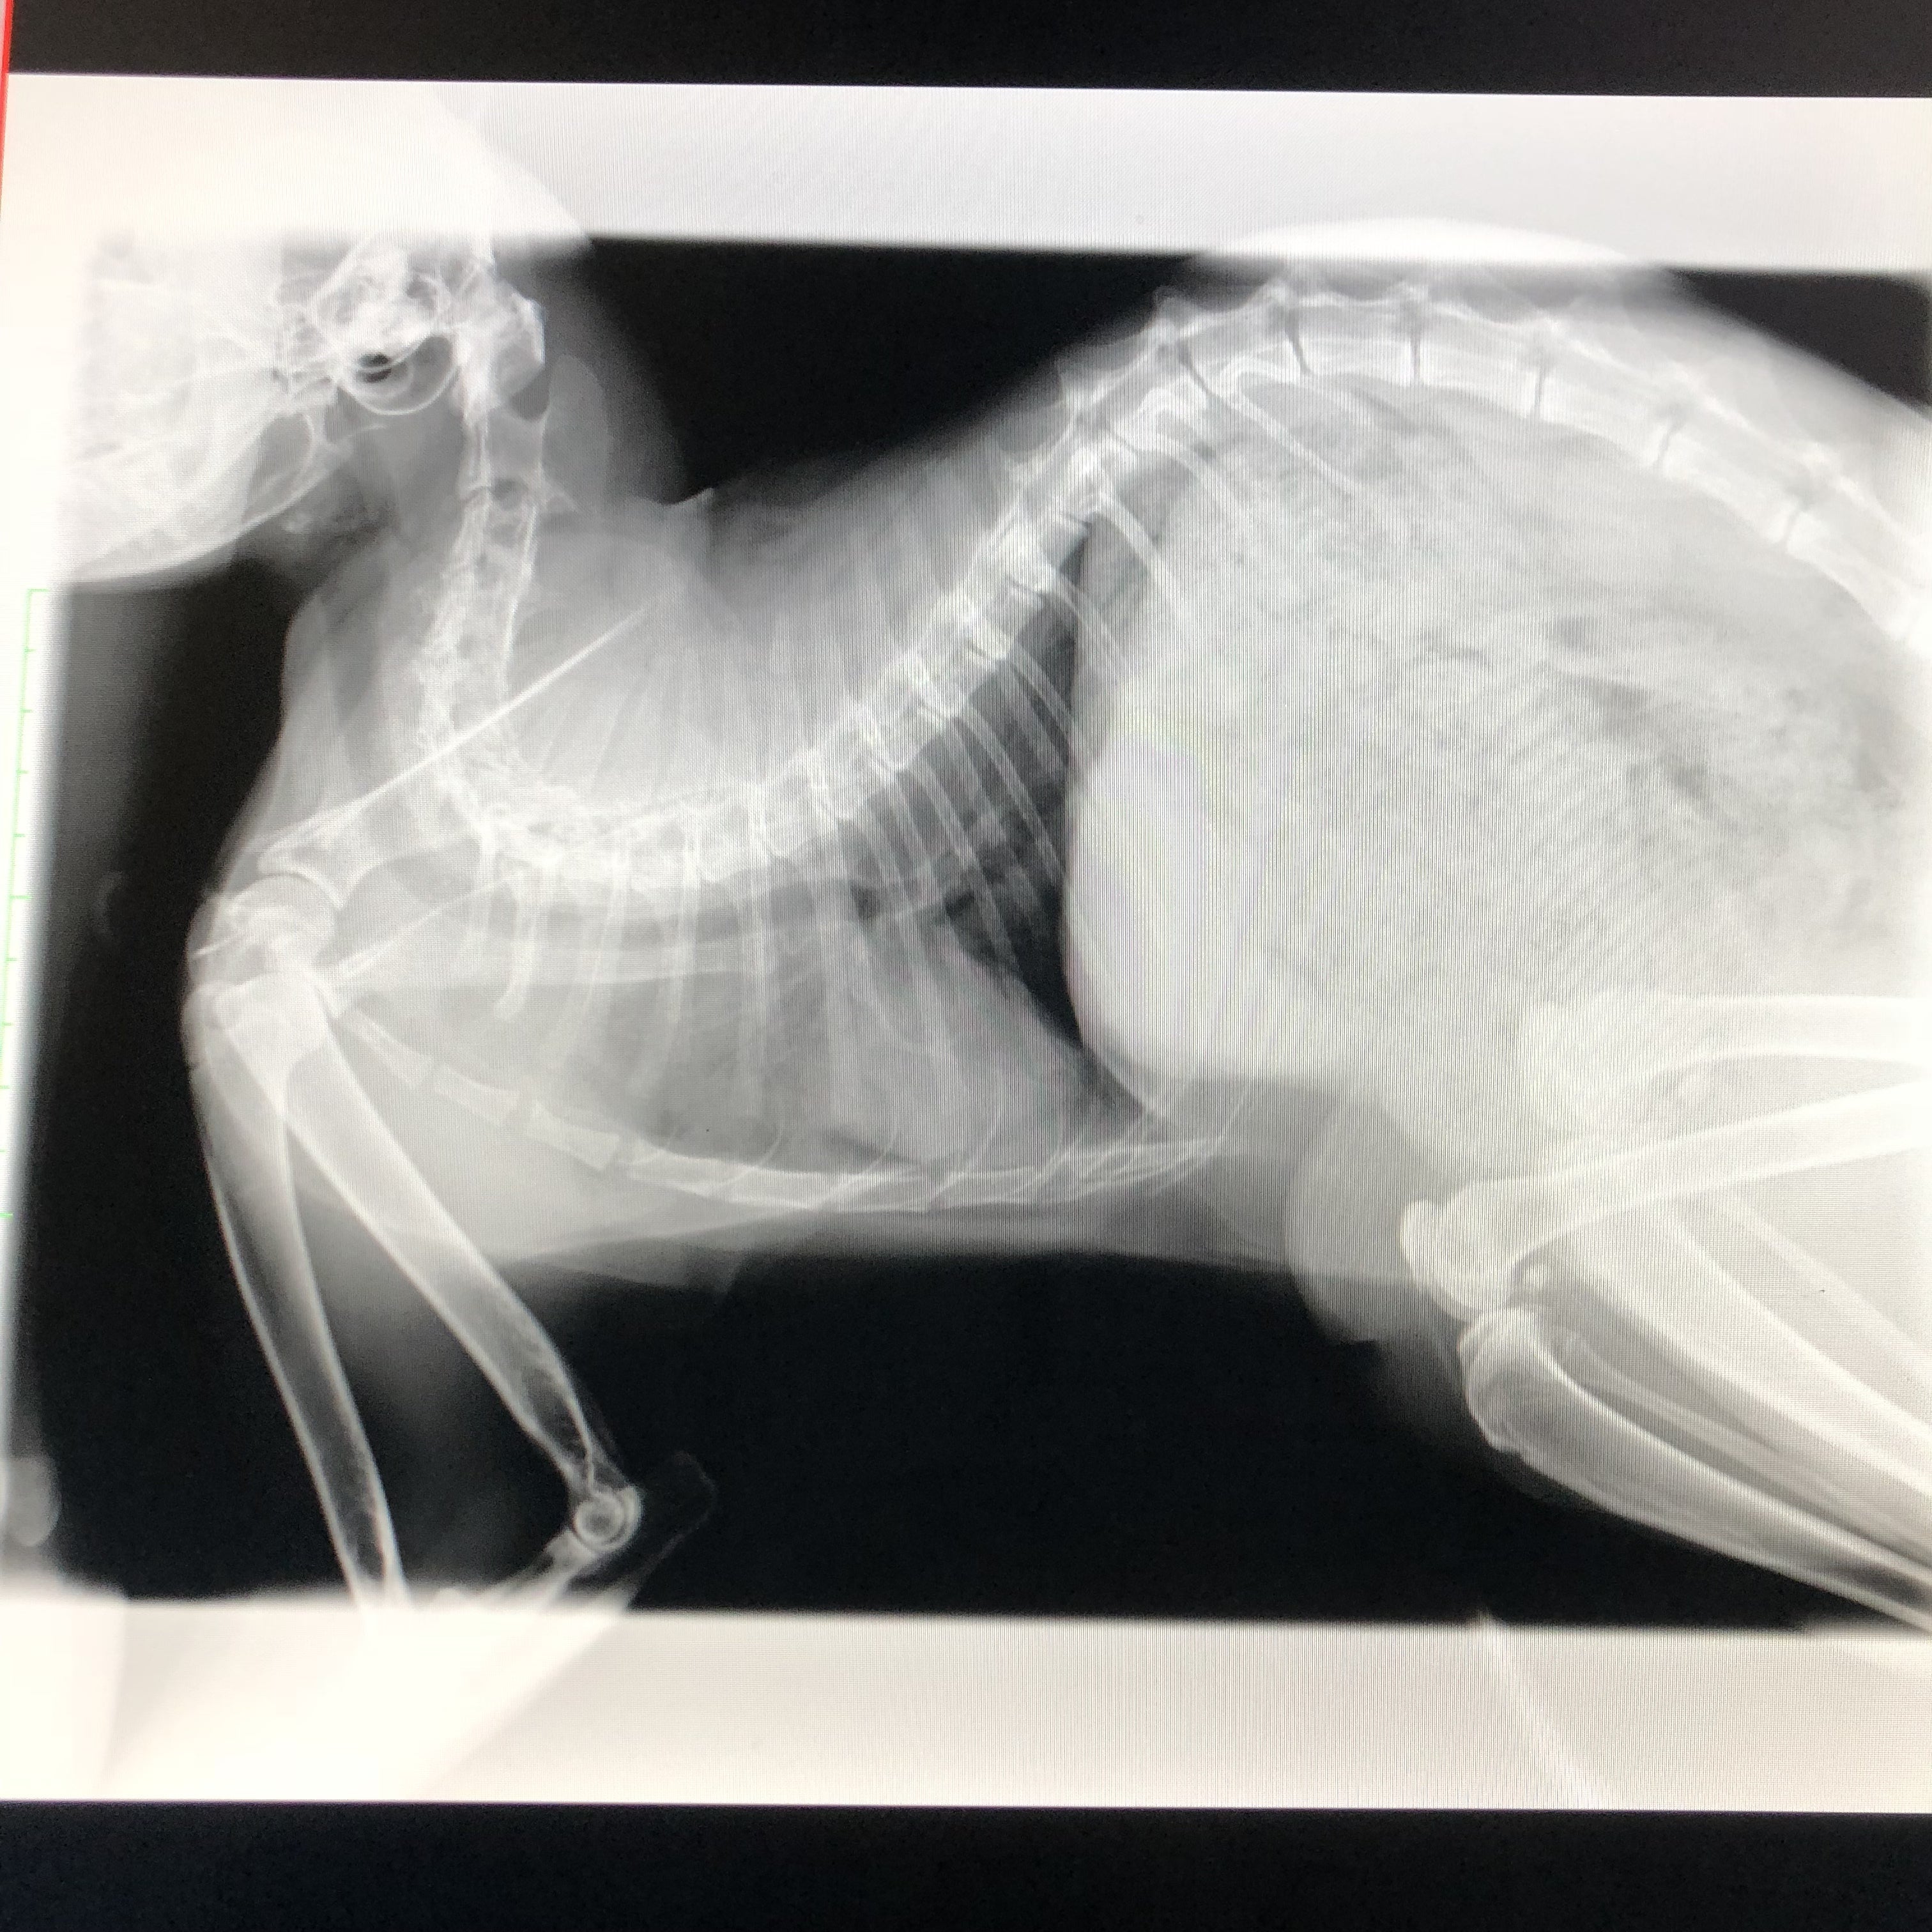

カイちゃん良い感じに抗がん剤とうまくいってます^_^副作用もあまりなくこれてます!これからが勝負でしょうが…明日は5回目の抗がん剤、そして年末本当は31日が6回目の予定ですが病院がお休みの為30日に7回目です。目標額までまだまだ程遠いのですが、残り10日を切りました( T_T)中々厳しいですね笑これまでかかった費用をまとめますここまでは検査でかかった費用です、¥142495抗がん剤開始4回目からは病院が変わりました抗がん剤4回目もでで合計¥171723です検査代、抗がん剤の全ての合計が¥314218です。これからまだまだ半年の計画で抗がん剤をしていきます、そして免疫力や体力をつけるための漢方やサプリも続けたいです、今のままクラウドファンディングが終了してしまうと大変厳しい状況になってしまう( T_T)お願いばかりではありますが、拡散のご協力をよろしくお願いいたしますそして、パトロンになる事を迷われている方、どうかご協力をよろしくお願いいたします、偽りなく収支報告等はさせて頂きます。